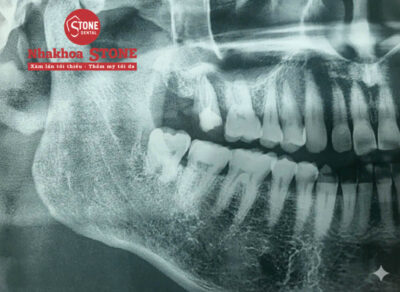

Kết quả thăm khám: Răng khôn mọc thẳng hoàn toàn so với trục của răng số 7.

Nguyên nhân gây đau: Dù mọc thẳng, nhưng do nằm quá sâu trong cùng, chiếc răng này bị nướu che phủ một phần (lợi trùm), tạo thành “túi chứa” thức ăn. Việc vệ sinh không thể chạm tới dẫn đến viêm nhiễm, sưng tấy và có mủ